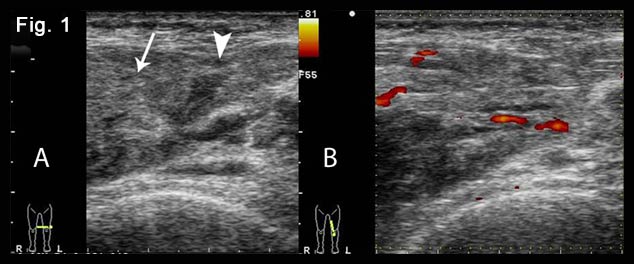

Figure 6. Confirmation of ultrasound findings with MRI.

Axial (A) and coronal (B) ΜR image of the injured muscles and suprapatellar recesses